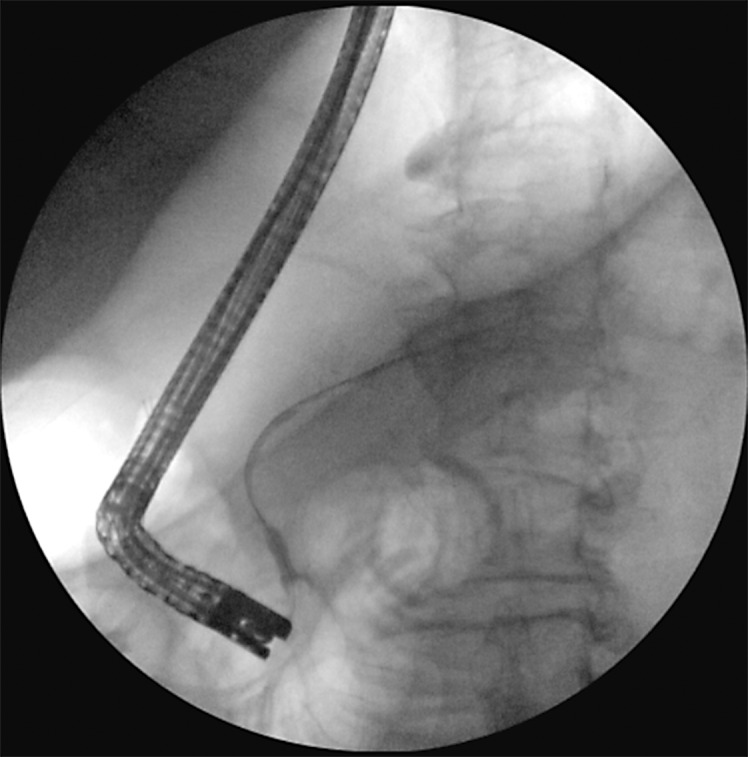

Case presentation: We present the case of a 79-year-old male with severe colitis resulting in perforation and pericolonic abscess formation adjacent to the pancreas, which resulted in an internal pancreatic fistula and pancreatic ascites. After 2 paracenteses, our patient ultimately underwent endoscopic retrograde cholangiopancreatography (ERCP) with sphincterotomy and pancreatic duct stent placement. The patient clinically improved and was ultimately discharged.

Conclusion: Follow-up ERCP was performed 2 months after discharge and showed no contrast extravasation, illustrating closure of the previous pancreatic fistula. Ultimately, our case demonstrates that cases of severe colitis may contribute to adjacent pancreatic fistula and ascites formation.